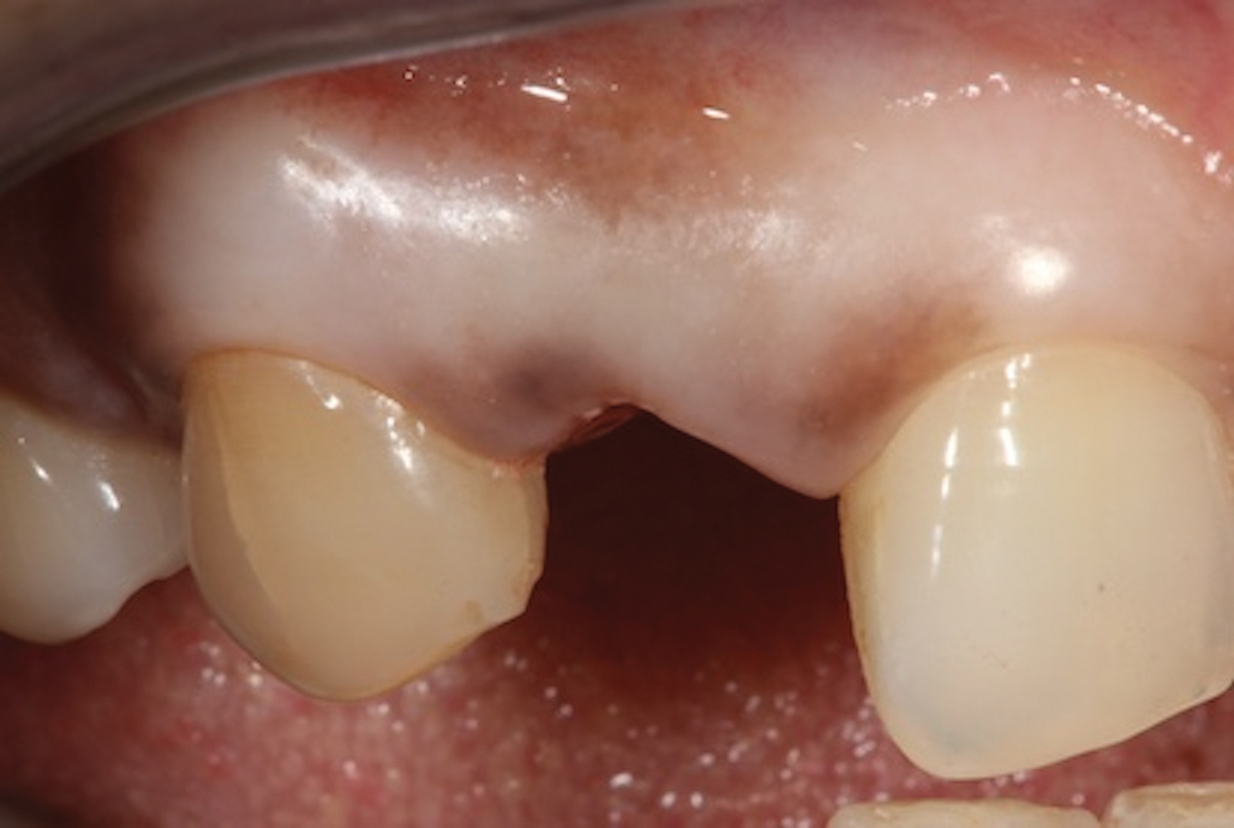

(3.) Placement of a rubber dam to achieve isolation.

Figure 3

1. Isolate the Operating Field

For any adhesive procedure, optimizing bond strength hinges on achieving proper isolation of the operating field. Placing a rubber dam ensures a pristine and fluid-free field, creating an ideal environment for both bonding and the subsequent development of the resin bridge (Figure 3). Achieving complete isolation is particularly important in cases involving replacement of a missing tooth immediately after extraction or implant placement.